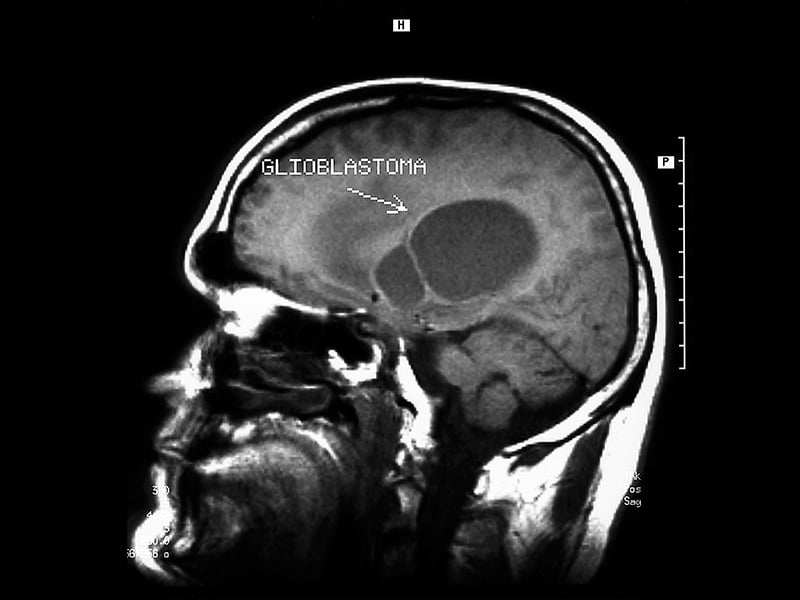

Radiation therapy is the primary tool to target tumors inside patients’ bodies. As the radiation strikes human tissue, it produces highly energized ions that gradually shrink and destroy the nucleus of malignant tumor cells. However, it’s targeted so it doesn’t damage the surrounding tissue.